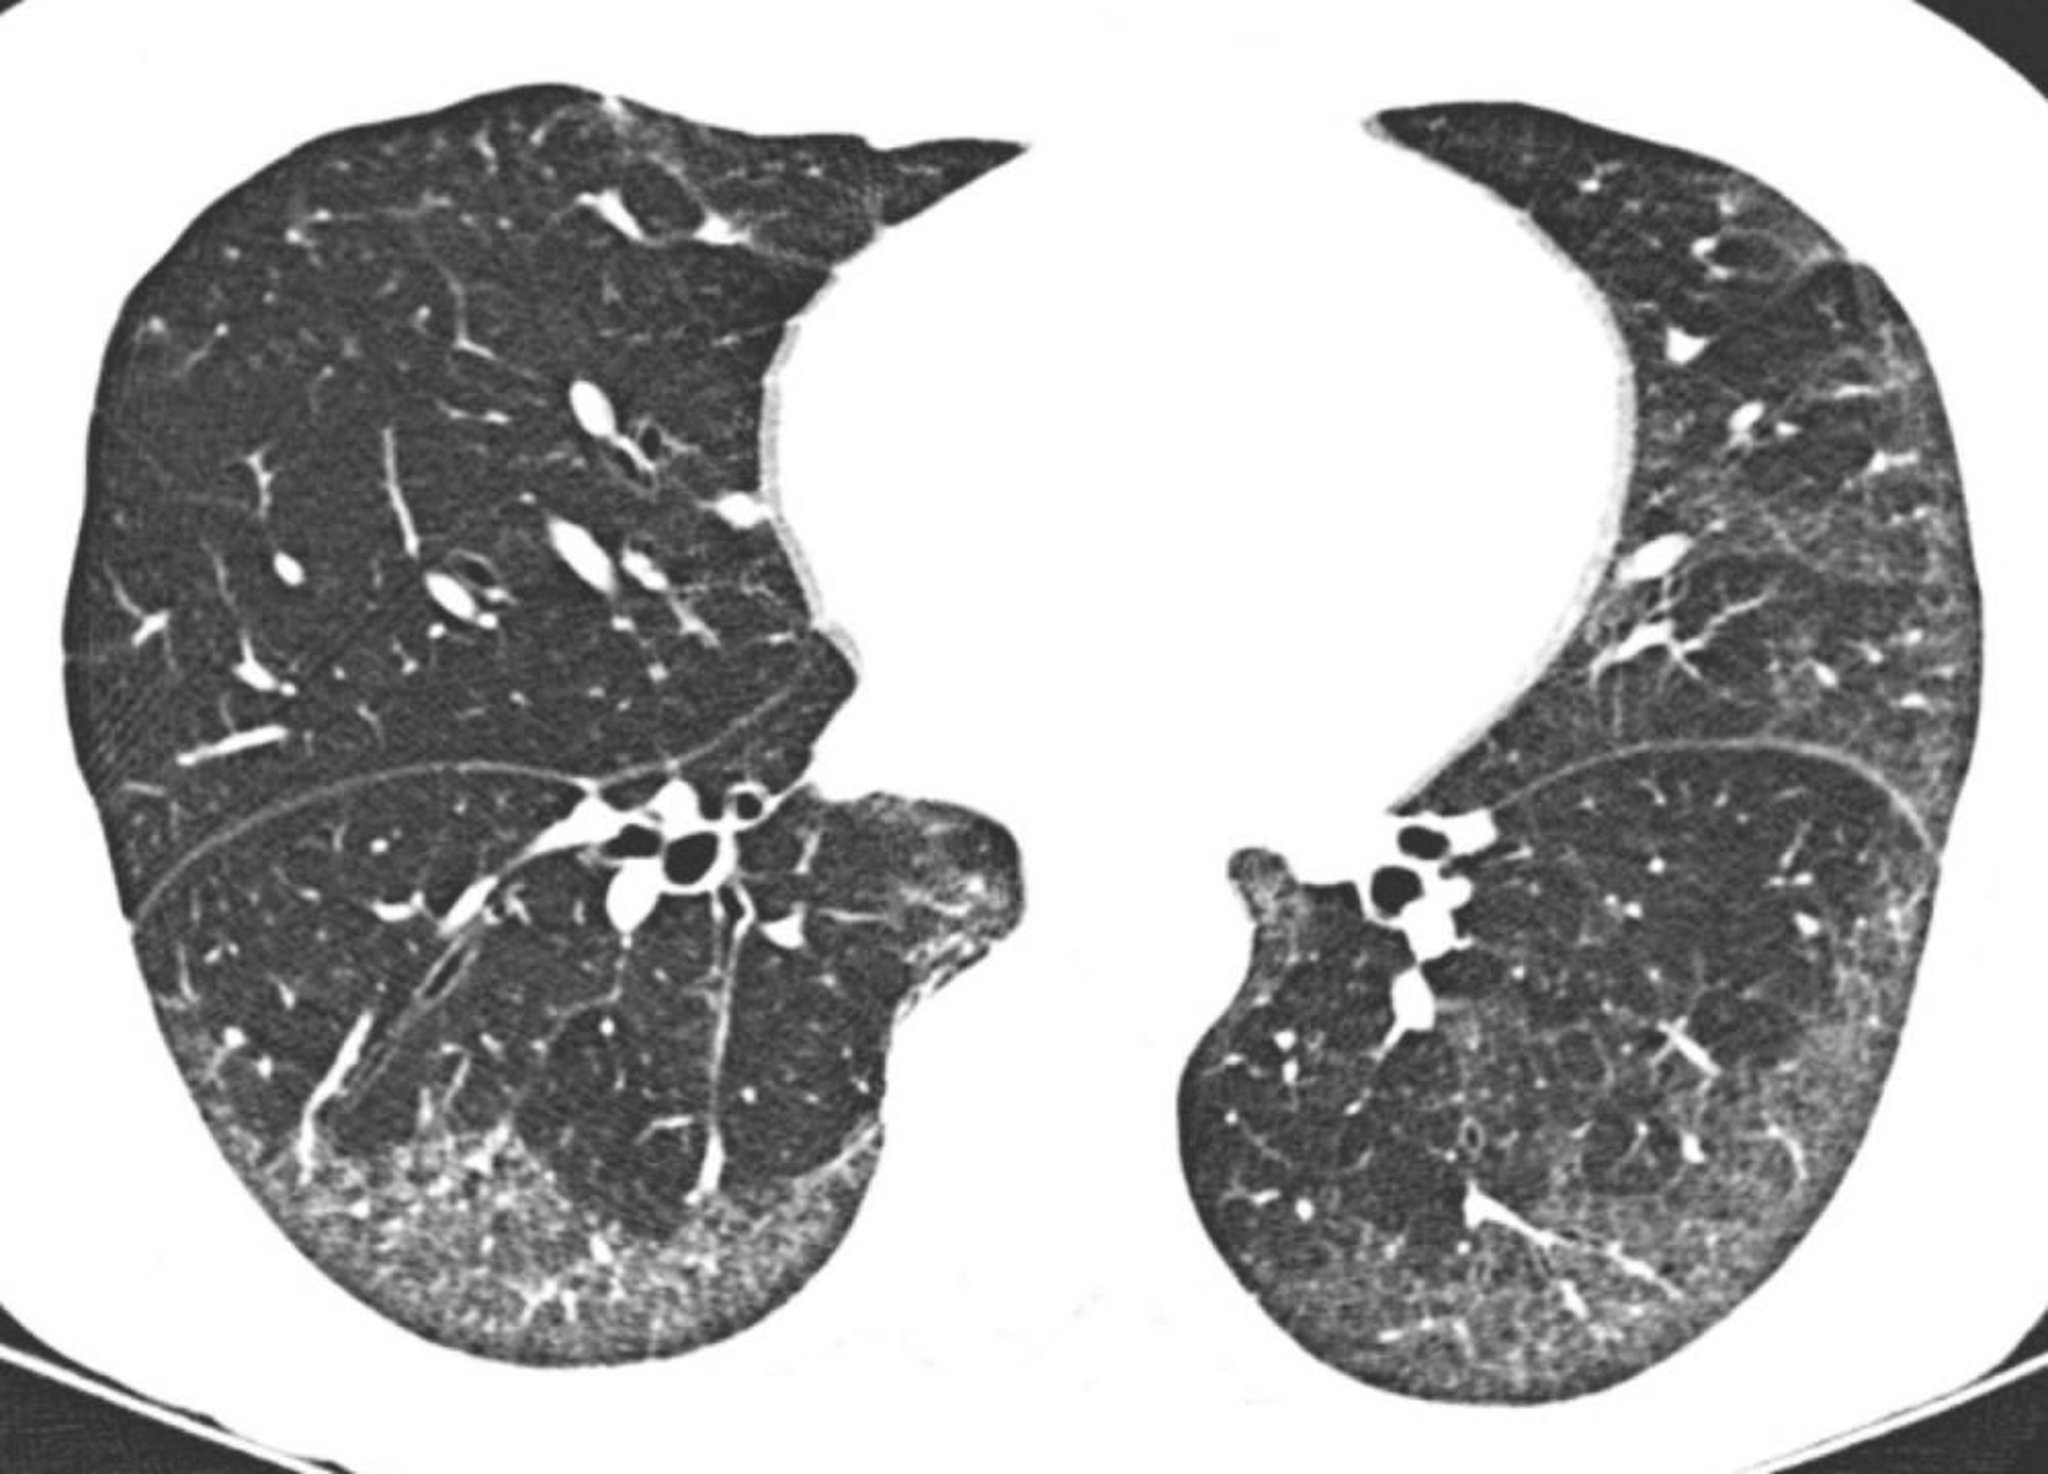

Viêm phổi kẽ không đặc hiệu tự phát

CT độ phân giải cao cho thấy chủ yếu là hình ảnh kính mờ ở dưới màng phổi hoặc ở đáy phổi. Không tổn thương phổi liên quan ngay dưới bề mặt màng phổi là điển hình trong viêm phổi kẽ không đặc hiệu.

Hình ảnh do bác sĩ Harold R. Collard cung cấp